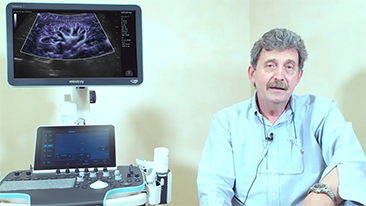

Aparaty ultrasonograficzne z serii Resona, dzi?ki szerokiej gamie za pomoc? wszechstronnych sond do r√≥?nych zastosowaŇĄ i wydajnych narz?dzi do zastosowaŇĄ klinicznych, pomagaj? U?ytkownikom stawia? dok?adniejsz? i efektywniejsz? diagnoz? oraz ocenia? wyniki.

Wspó?czesna rzeczywisto?? medyczna jest bardzo wymagaj?ca. Nieustannie wzrasta liczba trudnych przypadków i nak?adów pracy.